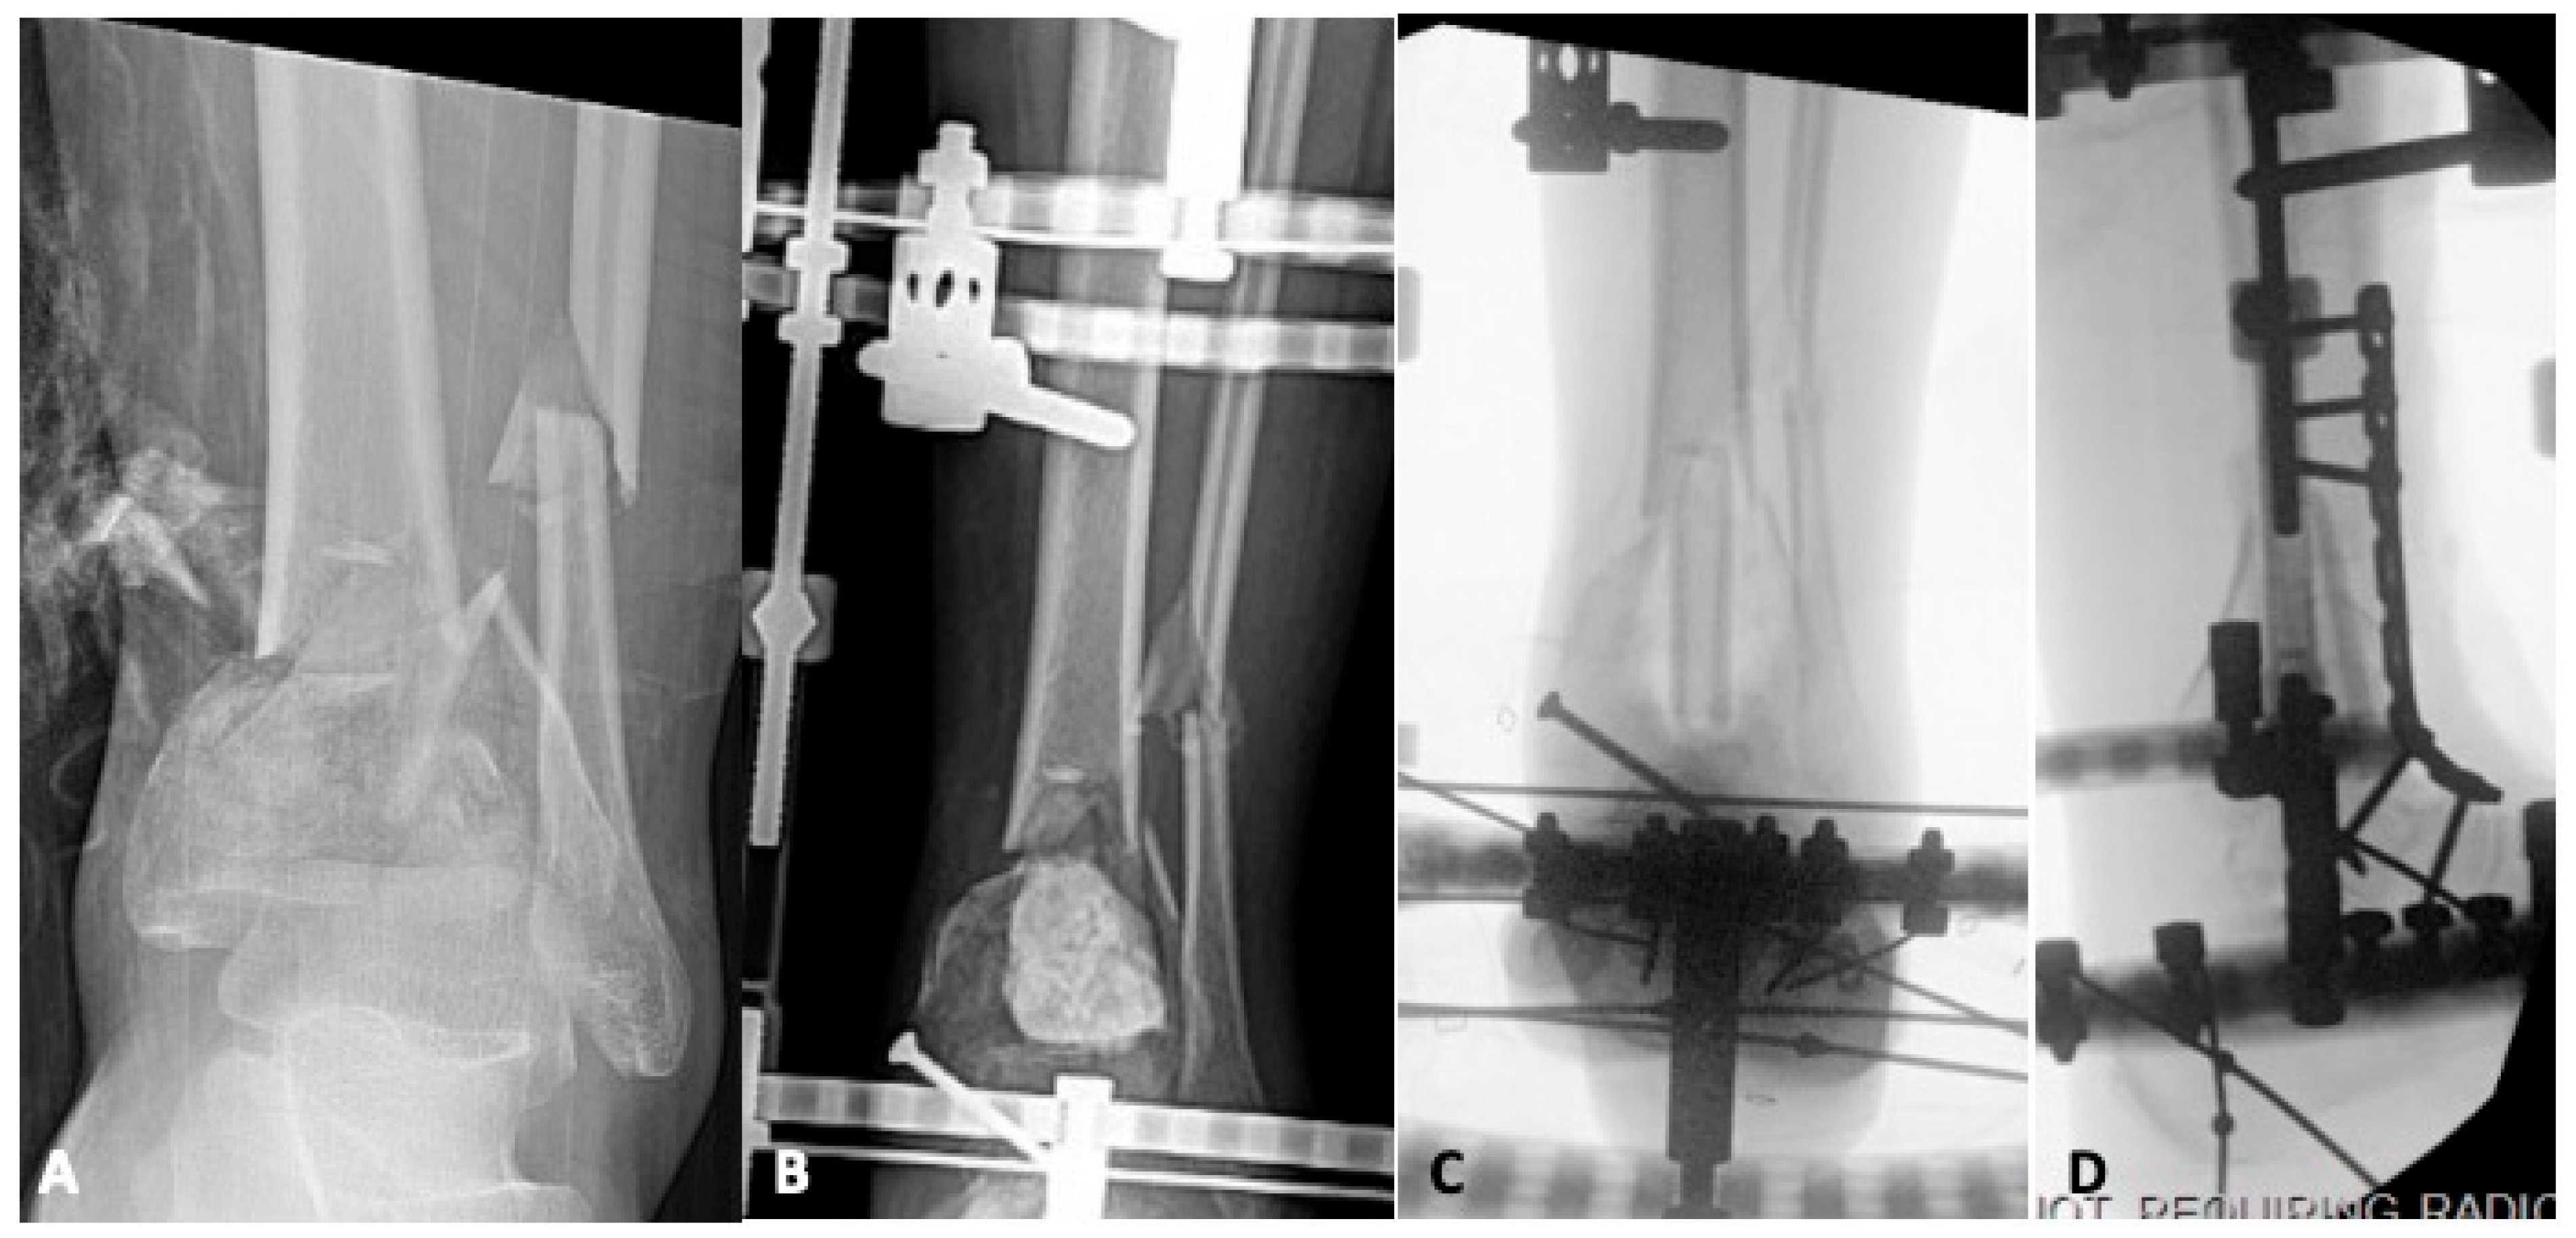

4.1. Infection

5.1. Revision Operative Fixation